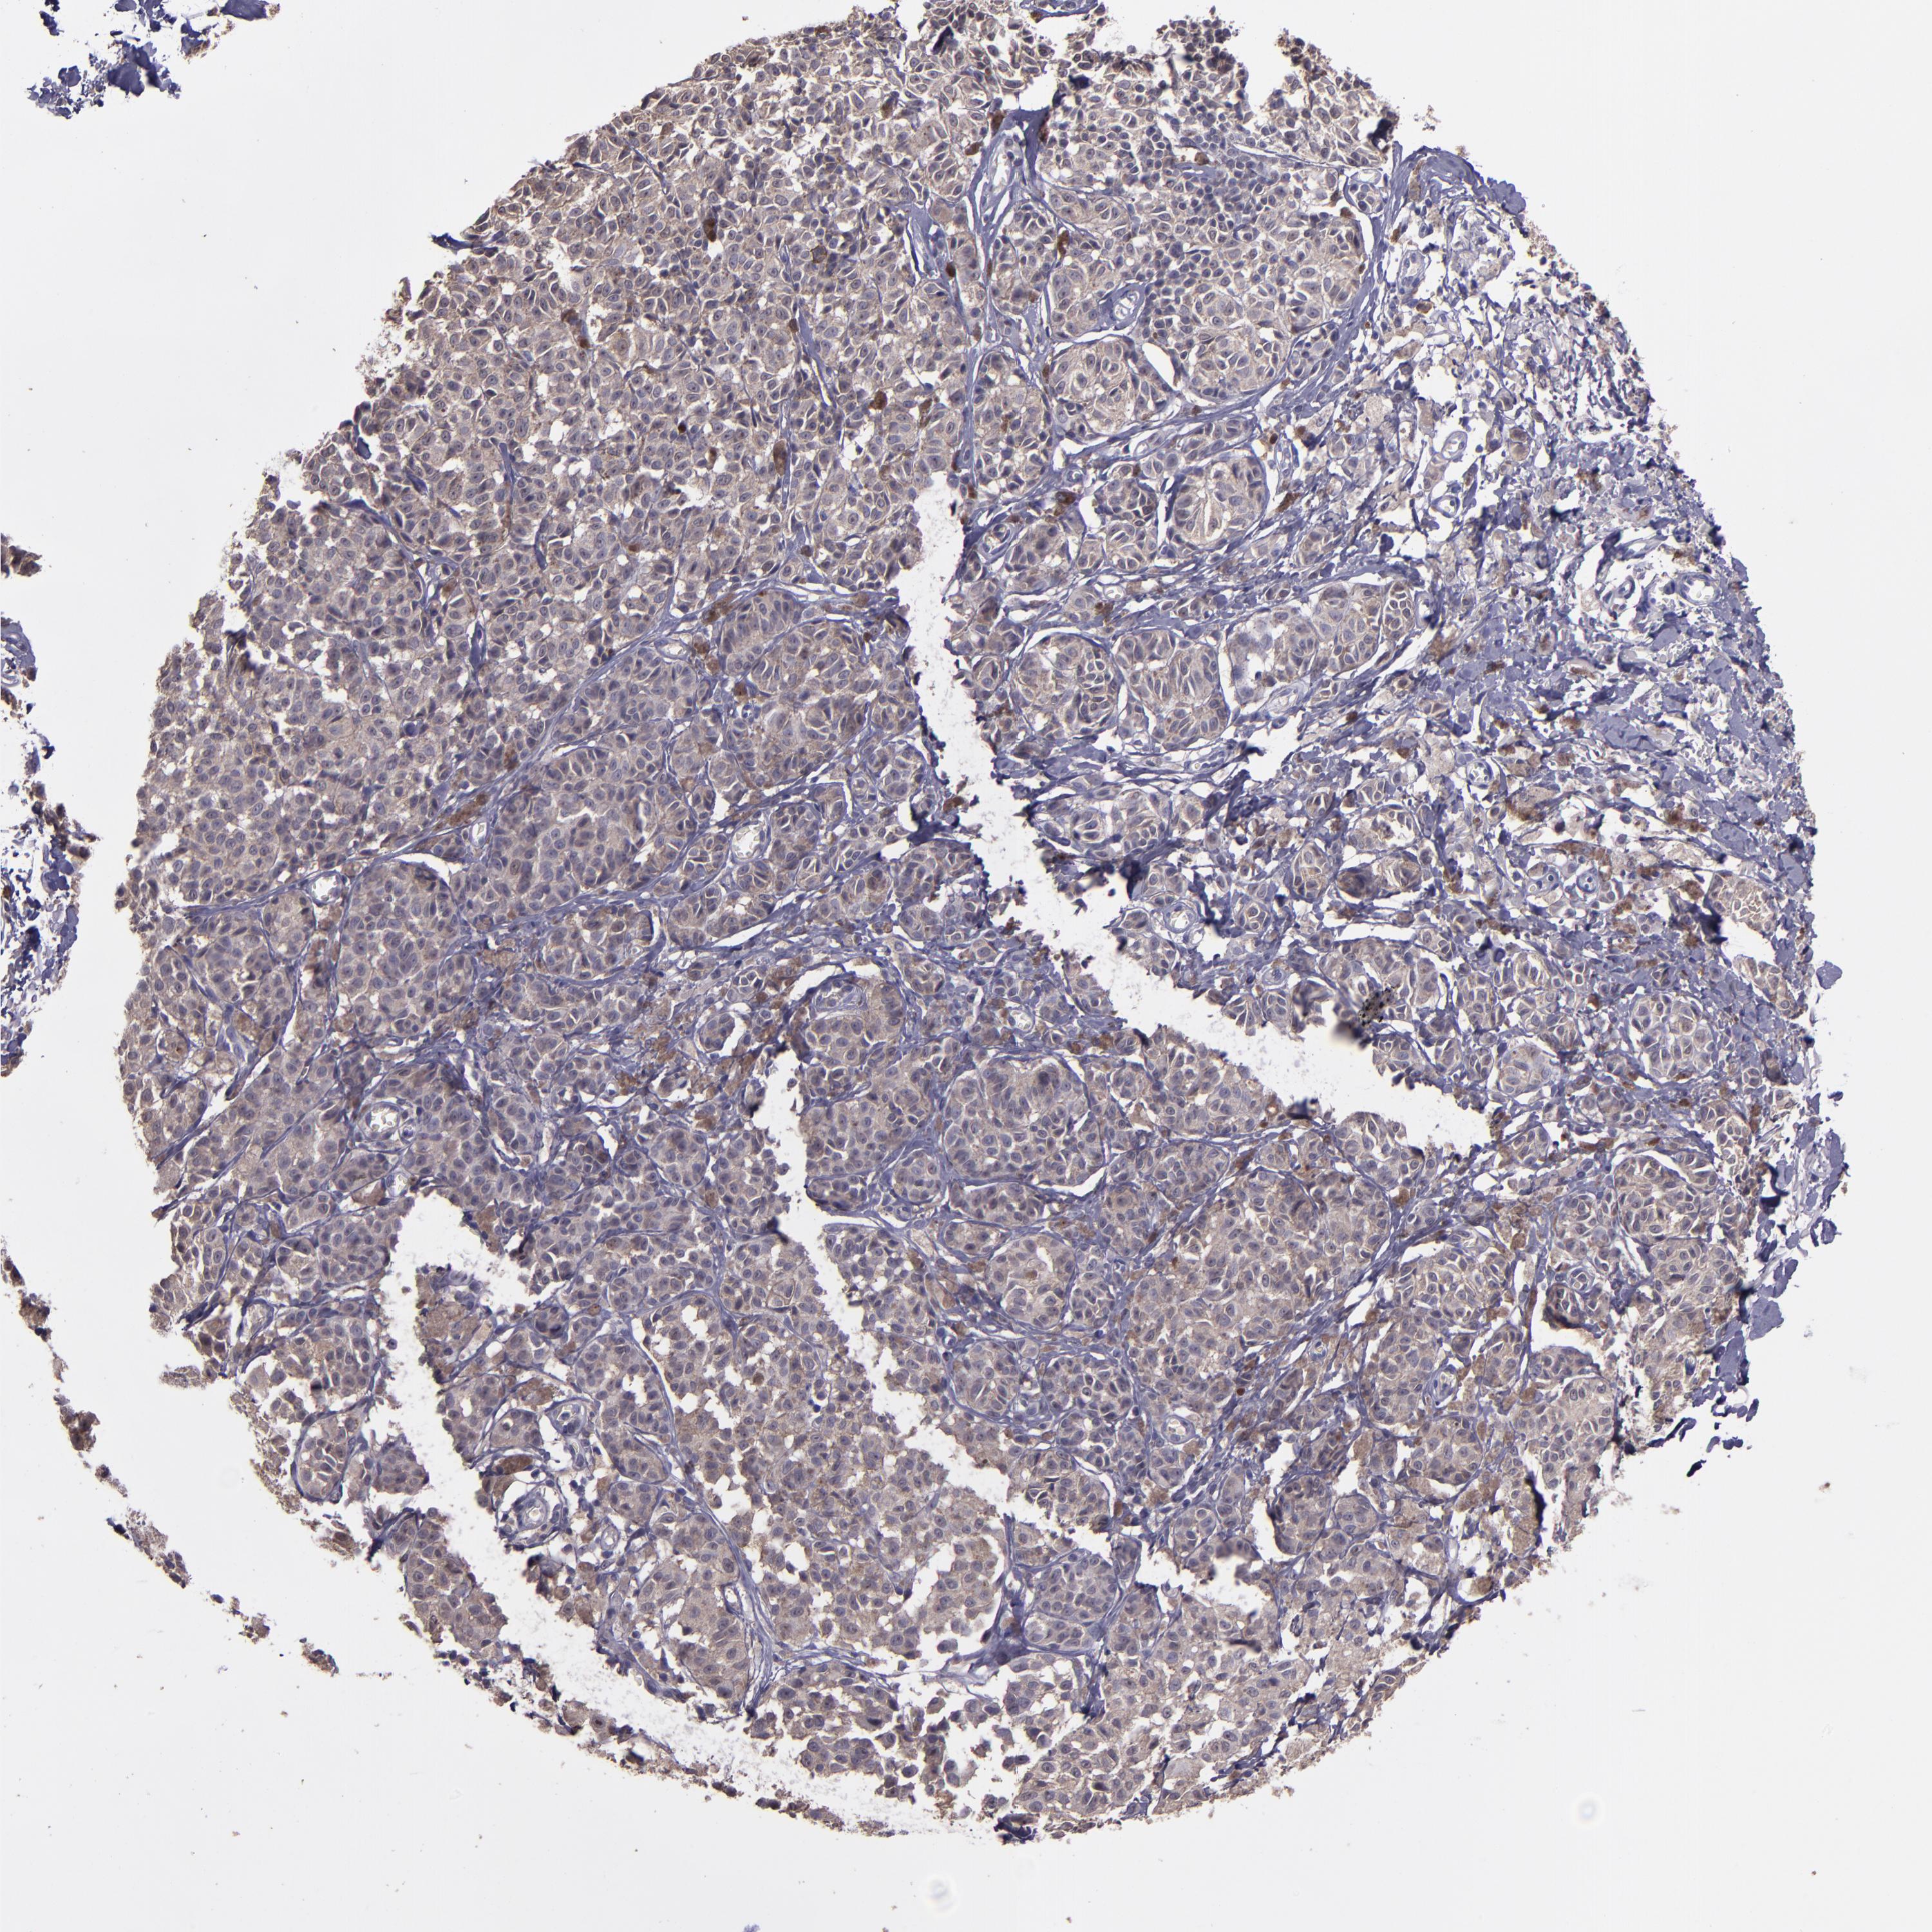

MELANOMA - Protein expressioni

A mouse-over function shows sample information and annotation data. Click on an image to view it in a full screen mode. Samples can be filtered based on level of antibody staining by selecting one or several of the following categories: high, medium, low and not detected. The assay and annotation is described here.

Note that samples used for immunohistochemistry by the Human Protein Atlas do not correspond to samples in the TCGA dataset.

Antibody stainingi

Antibody staining in the annotated cell types in the current human tissue is reported as not detected, low, medium, or high, based on conventional immunohistochemistry profiling in selected tissues. This score is based on the combination of the staining intensity and fraction of stained cells.

Each image is clickable and will lead to virtual microscopy that enables deeper exploration of all samples and also displays staining intensity scores, fraction scores and subcellular localization as well as patient and tissue information for each sample.

Antibody HPA001667

Antibody CAB016724

Staining

High

Medium

Low

Not detected

Intensity

Strong

Moderate

Weak

Negative

Quantity

>75%

75%-25%

<25%

None

Location

Nuclear

Cytoplasmic/membranous

Cytoplasmic/membranous,nuclear

Malignant melanoma, NOS

Malignant melanoma, Metastatic site